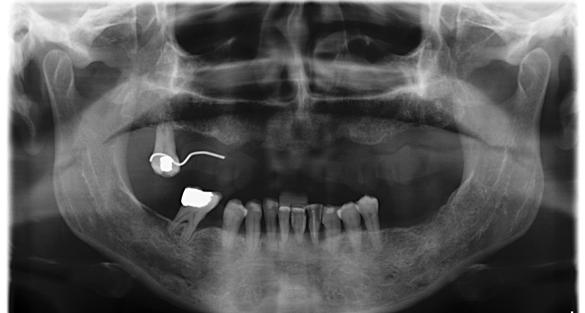

Figura 1. Radiografía inicial de la paciente. Se observa edentulismo total superior, a excepción del molar del primer cuadrante, indicado para exodoncia. En la mandíbula se aprecia pérdida ósea horizontal generalizada secundaria a la evolución de la enfermedad periodontal.

En la radiografía inicial (Figura 1) se observa la pieza 17 con pérdida ósea significativa, así como una reabsorción ósea homogénea a lo largo de todo el arco superior. En la arcada inferior se aprecia pérdida ósea horizontal generalizada y defectos localizados, como una lesión en cuña en la pieza 46. Ante esta situación, se decide realizar la exodoncia del molar remanente del

Figura 12. Radiografía final con la prótesis cementada en posición.

El mantenimiento periodontal y la implicación de la paciente en las medidas de autocuidado se mantuvieron de forma constante durante 23 años (Figura 25). La ortopantomografía realizada en una de las visitas de control mostró estabilidad completa de los implantes, sin signos radiográficos de pérdida ósea patológica.

Figura 21. Radiografía con la rehabilitación finalizada.

Figura 24. Radiografía a los 5 años que evidencia estabilidad ósea periimplantaria y periodontal.

25. Radiografía a los 25 años con mantenimiento del nivel óseo en implantes y dientes remanentes.